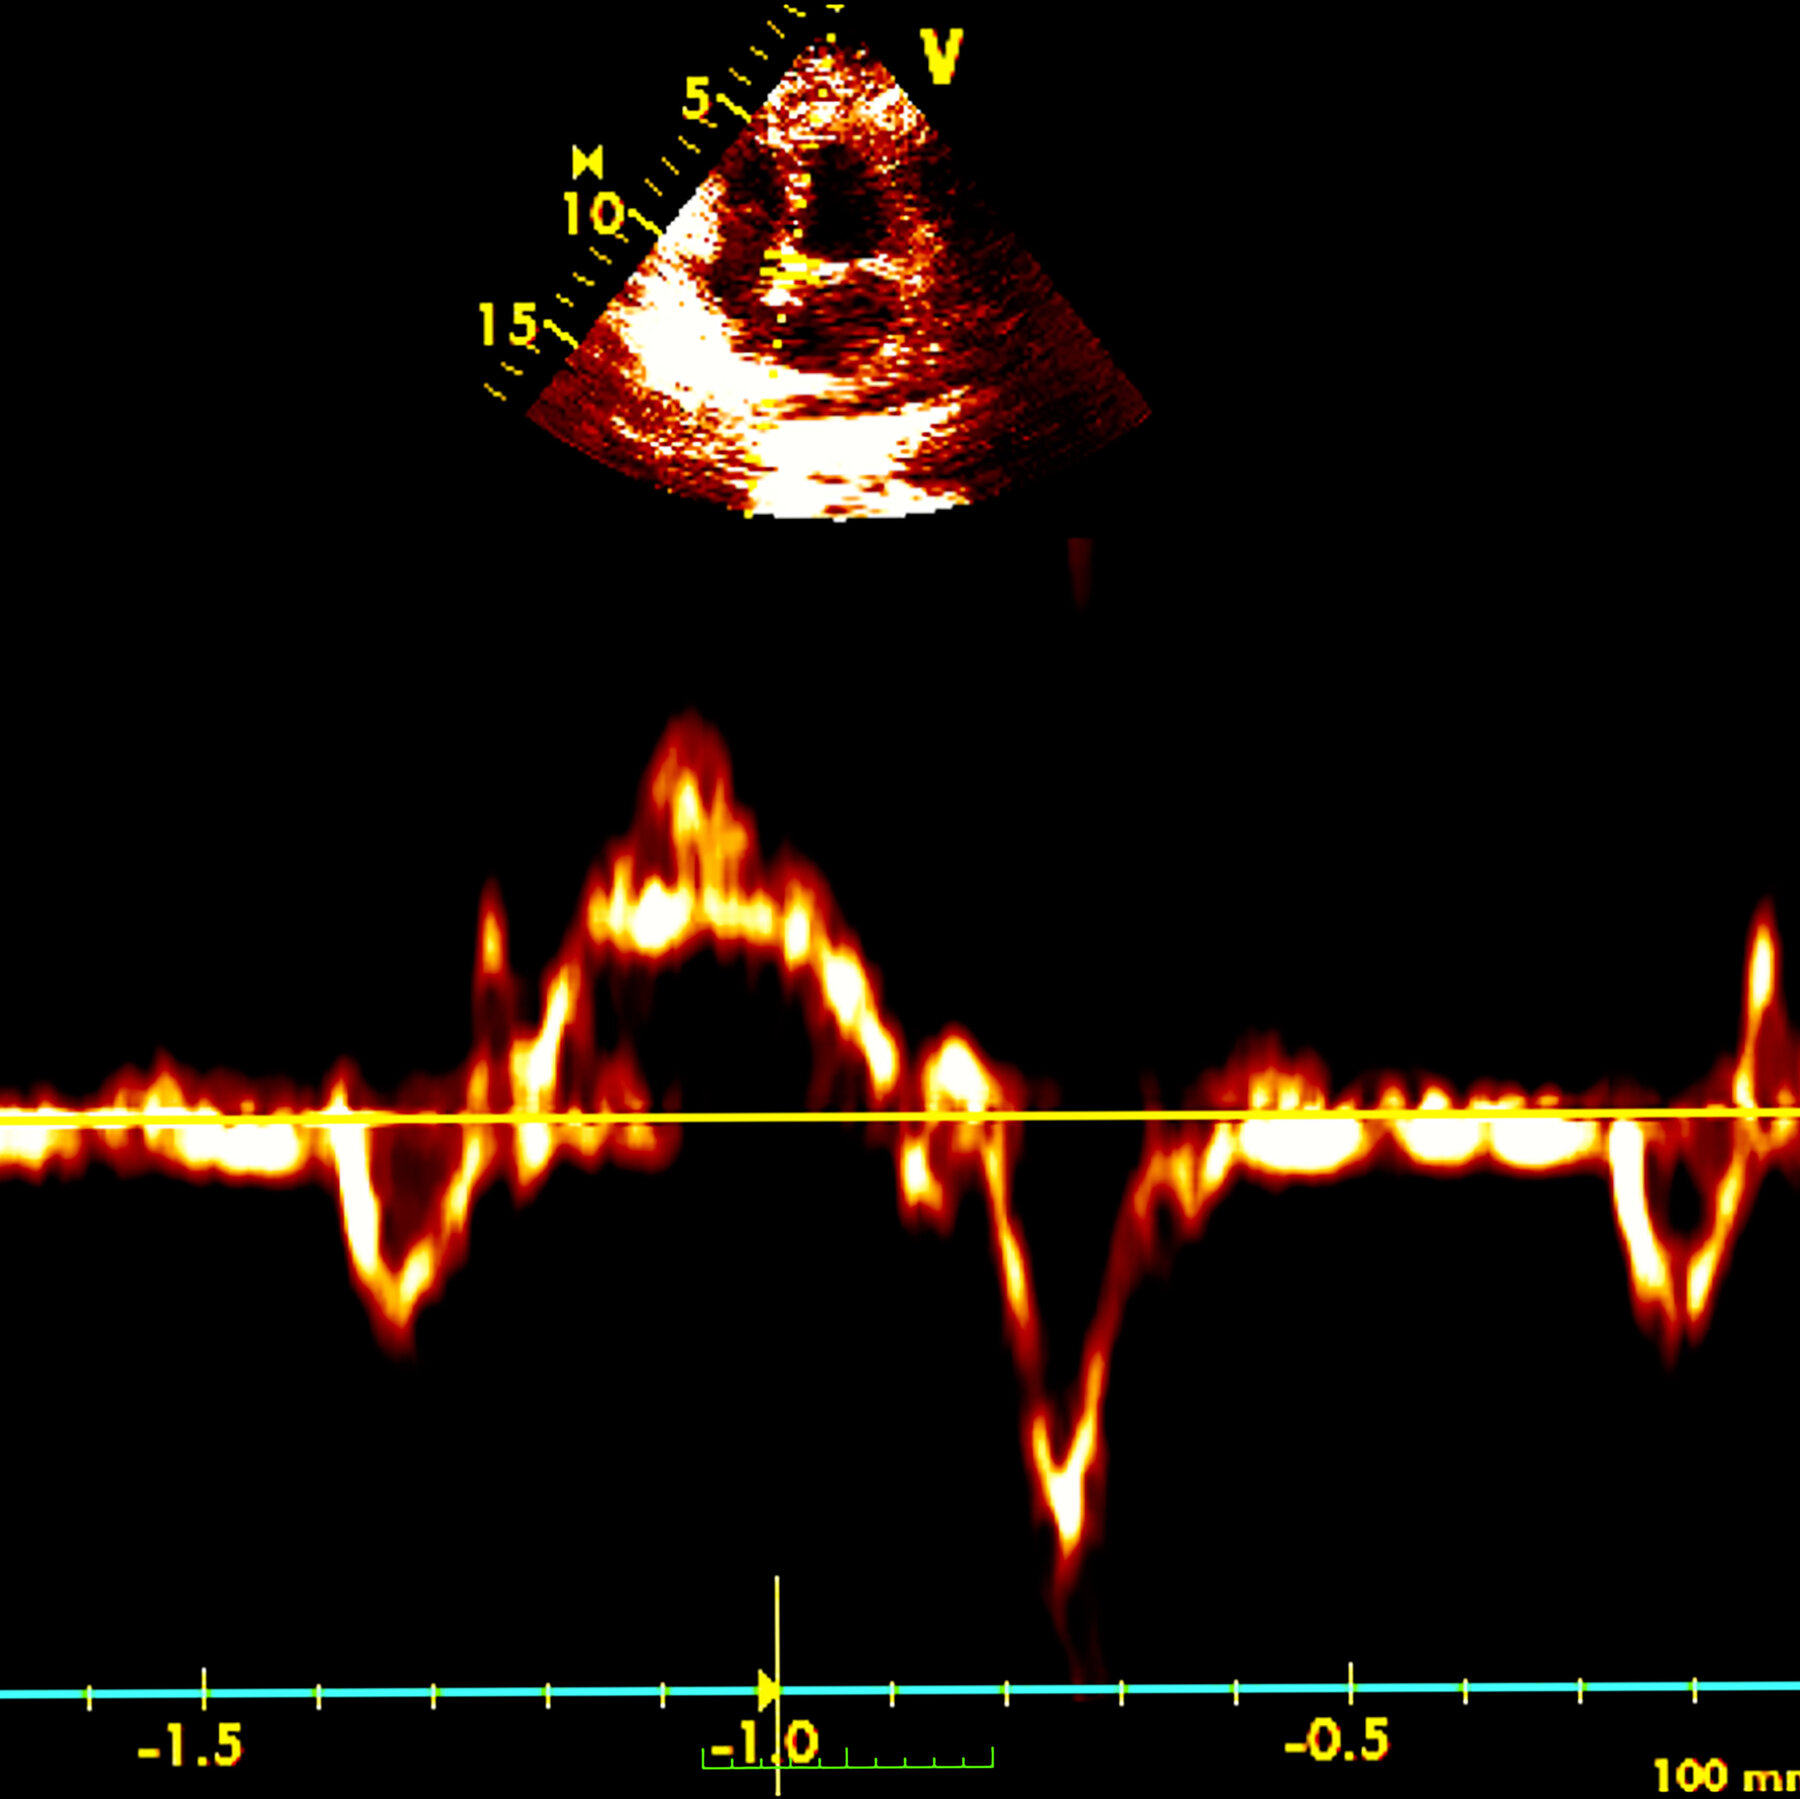

Women Who Undergo Menopause Before 40 Face Higher Heart Attack Risk

[unable to retrieve full-text content]A new study found that women who went through so-called premat ...View More

Women Who Undergo Menopause Before 40 Face Higher Heart Attack Risk

[unable to retrieve full-text content]A new study found that women who went through so-called premat ...View More